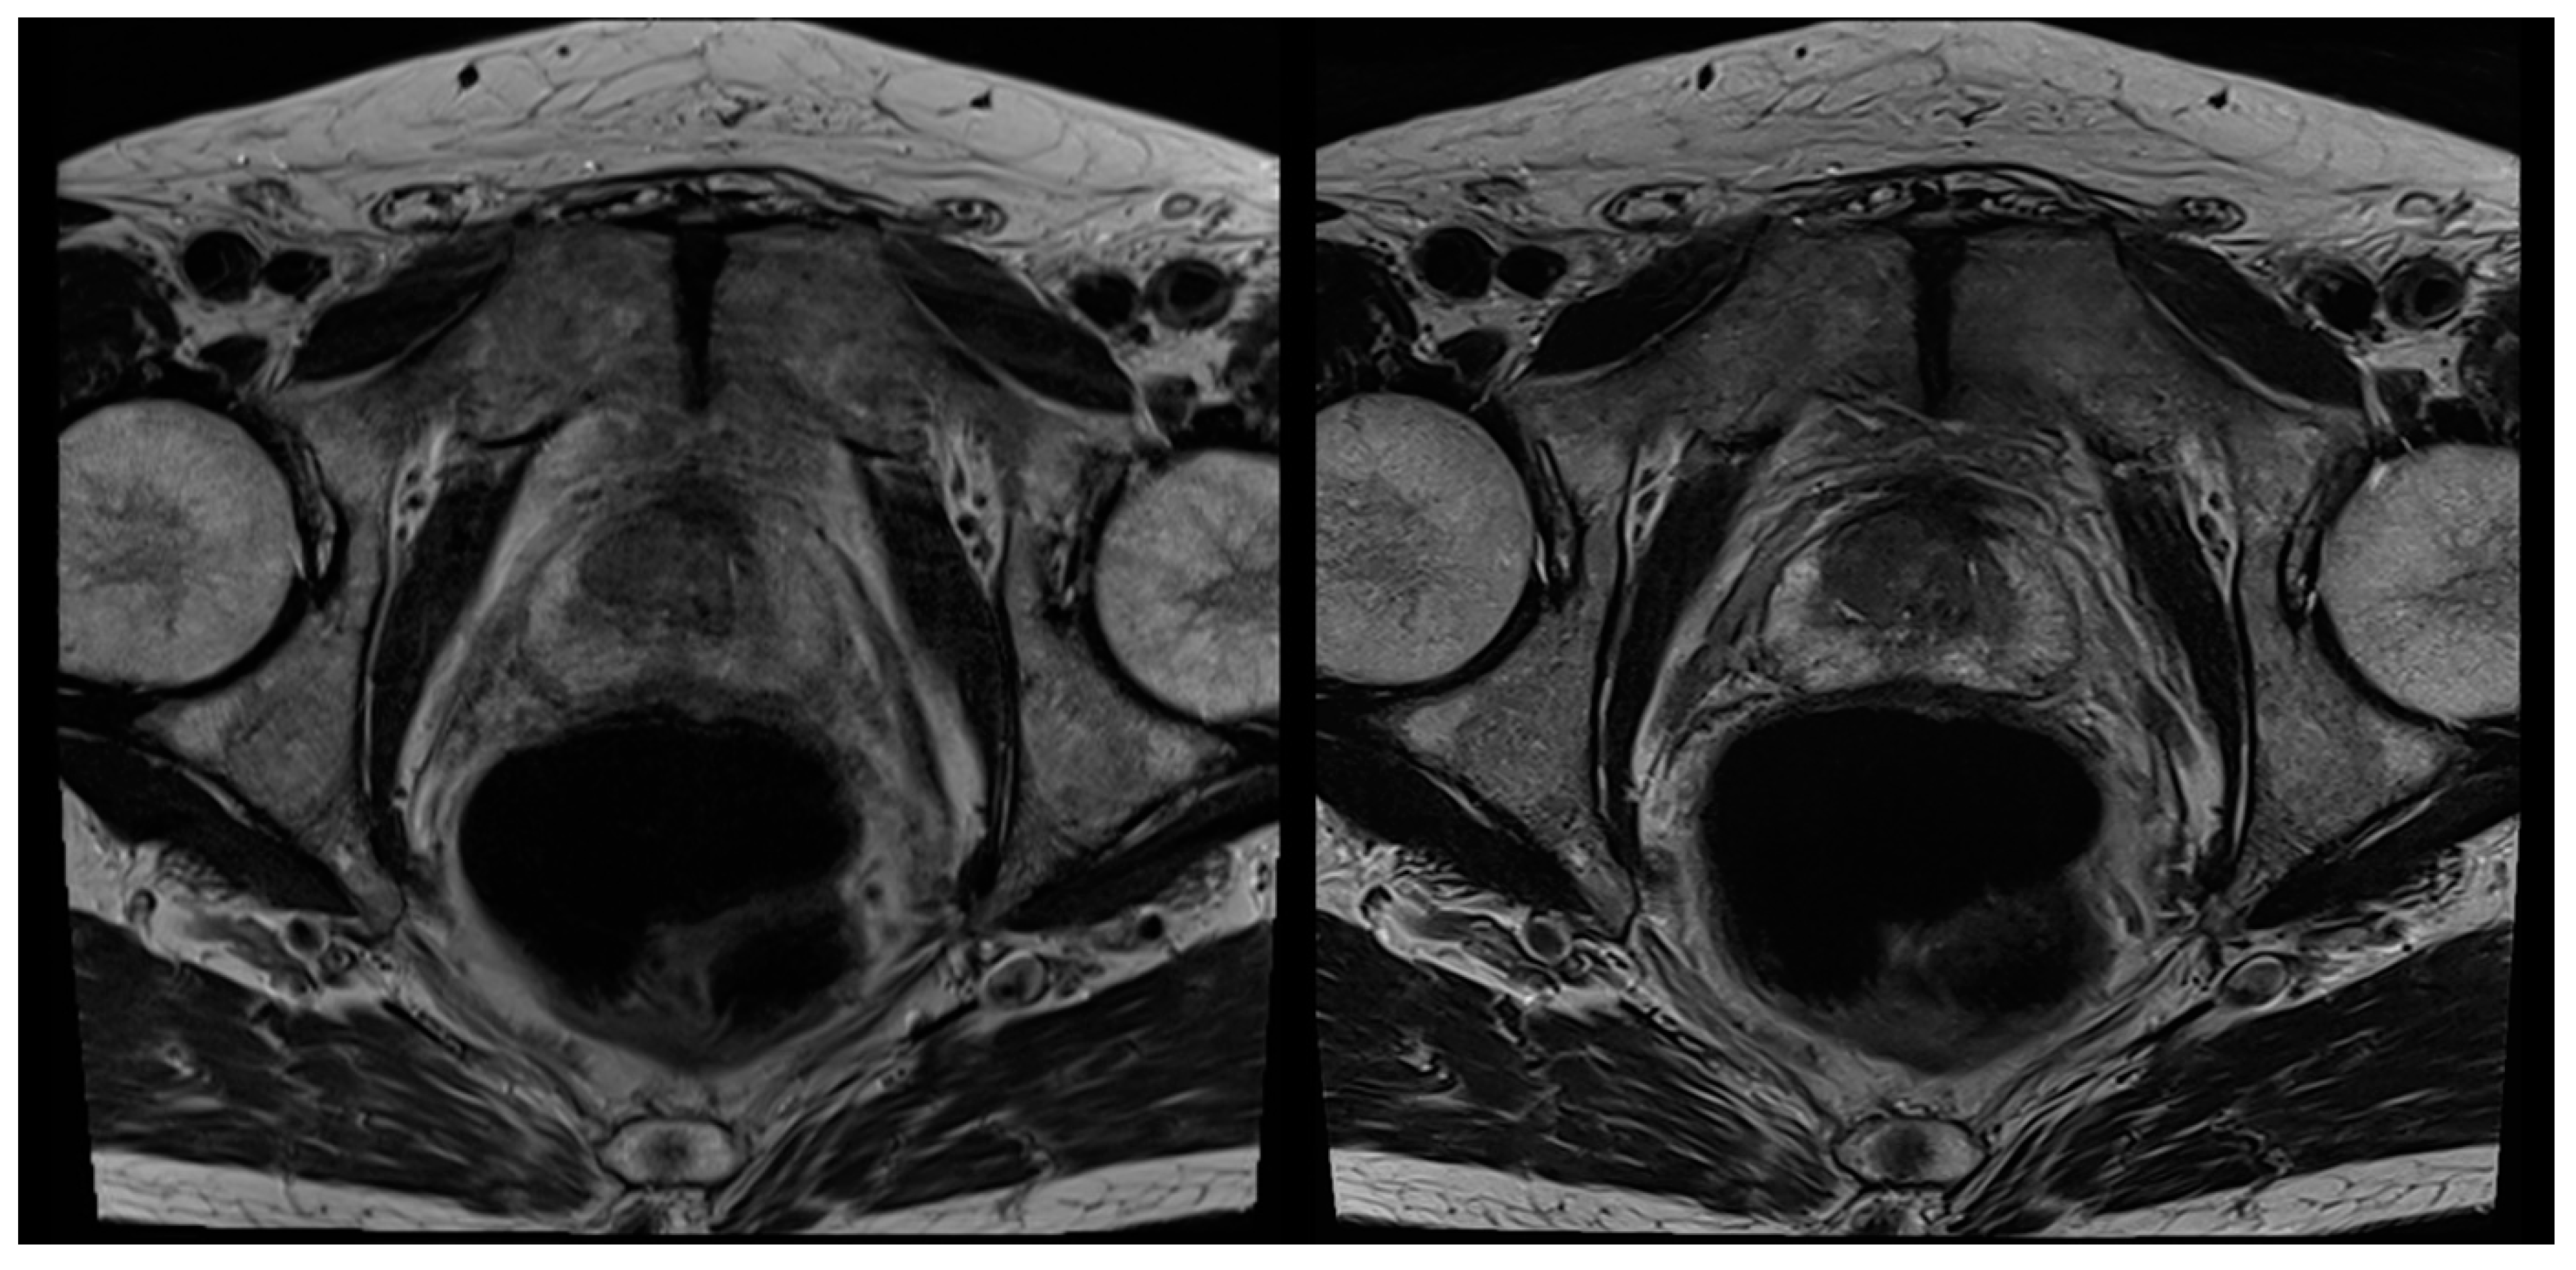

Figure 3. A 72-year-old male patient with suspicion of prostate cancer. Example of axial standard T2-weighted TSE imaging (T2S) on the left-hand side and deep learning–reconstructed (T2DLR) imaging on the right-hand side. Similar to Figure 2, less motion artifacts occurred in T2DLR with sharper depiction of the prostate.